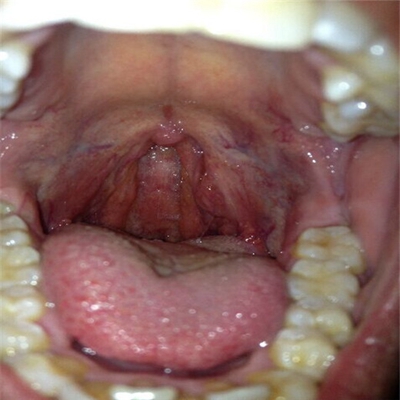

扁桃體惡性腫瘤圖片

扁桃體癌圖 (7)

扁桃體癌圖 (8)